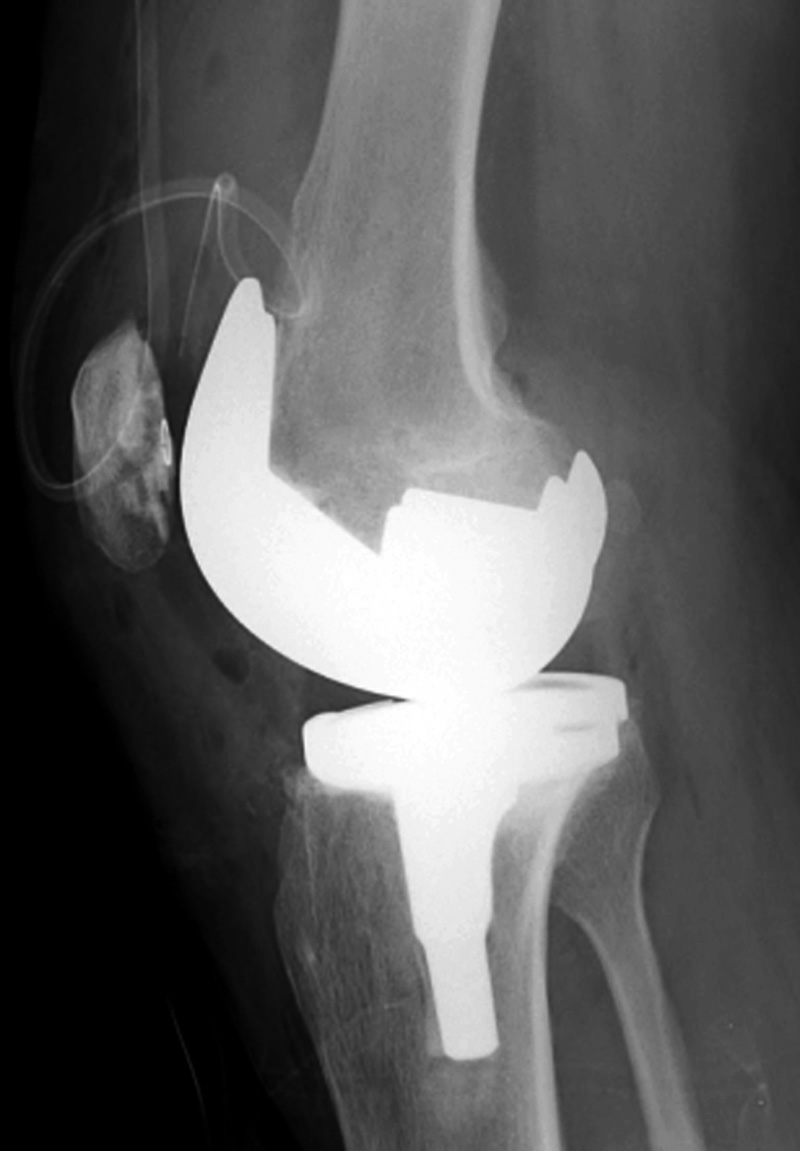

Left knee cruciate substituting revision total knee prosthesis   Cruciate substituting total knee prosthesis and patellar resurfacing.

Left knee cruciate substituting revision knee arthroplasty Left knee cruciate substituting revision total knee arthroplasty Cruciate substituting knee prosthesis - AP view Cruciate substituting knee prosthesis - latera view

46 year-old man with knee revision arthroplasty   Note the large distal femoral box. There is a surgical drain in the suprapatellar space. From Taljanovic, 2005